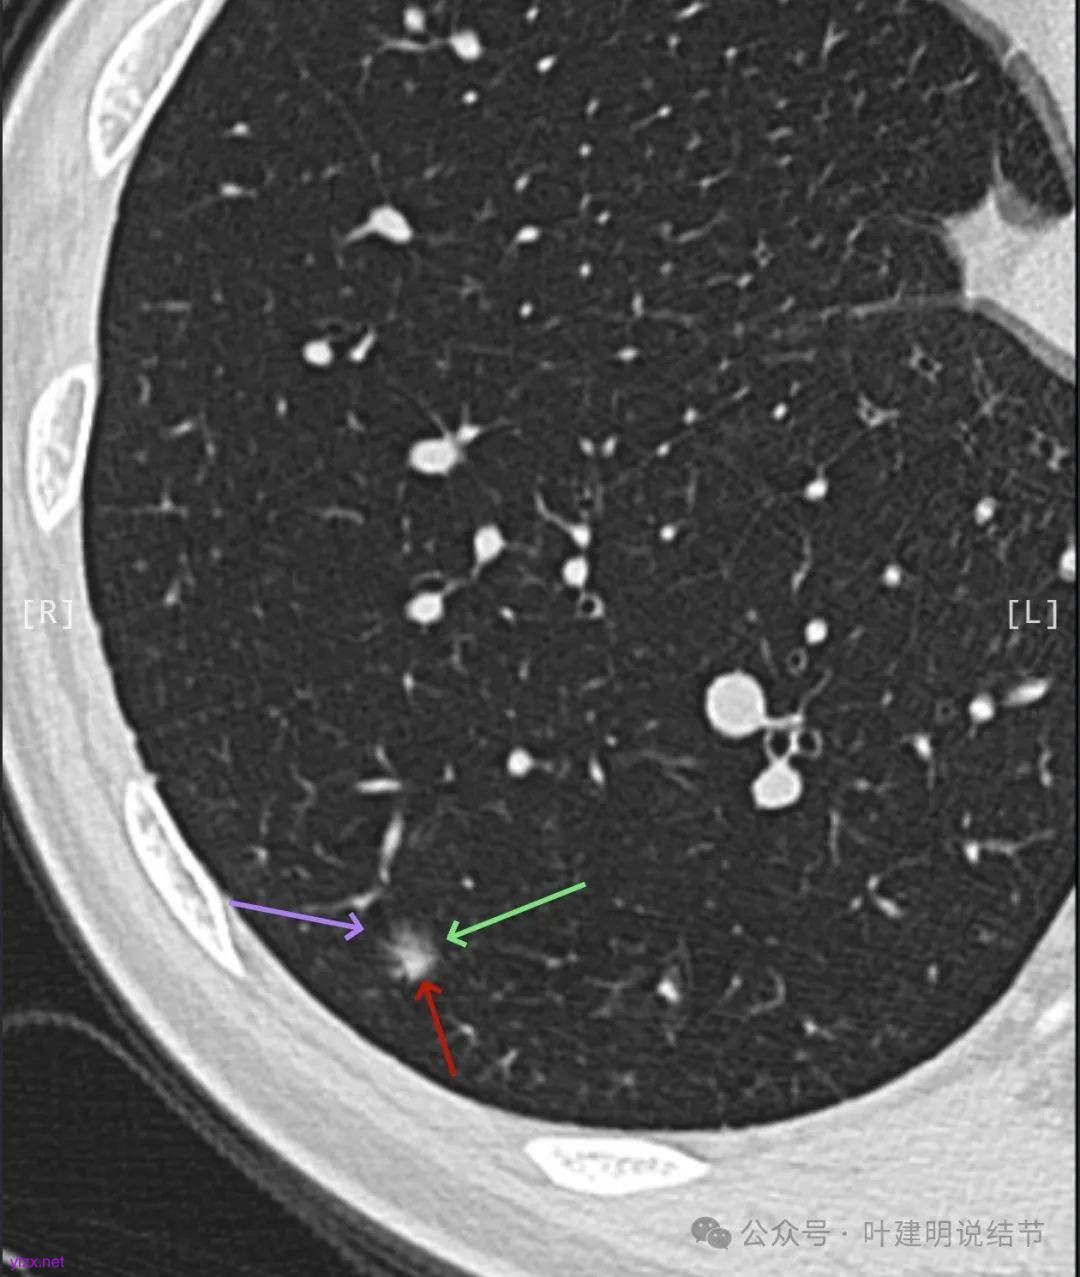

逐层看了2024年的影像:

我又建议其还是切了好。但嘱咐她不管病理是什么类型,只做楔形切除,因为毕竟7年才长这么点,浸润性癌也不会是恶性高会转移的亚型。

这个病例其实有反思回顾的价值,我想可以从中得出下面这些感想:1、混合磨玻璃结节随访持续存在且没有钙化或吸收好转,即使整体轮廓清,有血管征、有细支气管截断征、有毛刺与棘突征,且灶内密度杂乱,集齐许多恶性影像特征,仍不能下定论必为恶性;2、回头看病灶最终之所以不是恶性,而是慢性炎伴纤维增生与碳末沉积,最为关键的一是进展太慢,不符合混合密度结节含高密度实性成分的肺癌的生物学行为;二是实性部分密度过高而磨玻璃成分显得略偏模糊,看上去像有点晕征的味道。我反复总结过“混合密度实性成分过高而磨玻璃成分密度过低的容易是慢性炎或肉芽肿性炎伴纤维增生”。但临床的应用中仍不太敢下定论;3、多看几位医生也不能就100%明确。就如此例10位医生均考虑恶性范畴,虽有一位考虑原位癌,但其实也算是癌的范畴,但其实真正的影像上之所以判断的病灶部分不是肺癌,若牵强认为非典型增生与原位癌类似也可算浸润性病变,那也是碰巧而已,而不是从影像判断上看出有不典型增生,而密度高的却认定是良性成分;4、手术切除与否对于此例来说,仍是值得的,因为问了10位医生都说是肺癌,即使随访也压力巨大,而且密度不纯。从结果来看,已经存在非典型增生,继续随访,多年后也可能还是会发展成微浸润性腺癌或浸润性癌的可能性。而且楔切创伤不大,既明确诊断,也去除了病灶,是利大于弊的。当然这再次印证我一直坚持的原则:从风险高低来考虑手术与否以及干预的时机,而不要过于在意最后的病理结果。